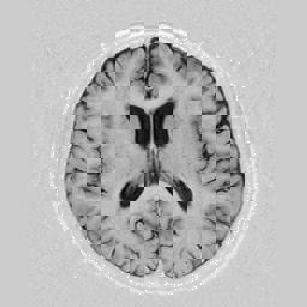

Lastly, Figure [*] shows 10 iterations at level 2, 6 iterations at level 1, and 6 at level 0.

Figure: Multi-scale NRR. From left to right, top then bottom: before NRR; after 10 iterations of NRR at level 2; after another 6 iterations of NRR at level 1; after 6 more iterations at level 0.